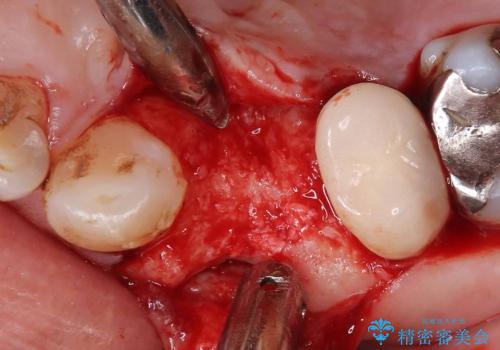

歯根破折により保存は不可と診断し抜歯後、骨ができるのを待ってインプラントで治療を行いました。

抜歯後、骨が出来るまで6ヵ月待ちその後インプラントを埋入しました。